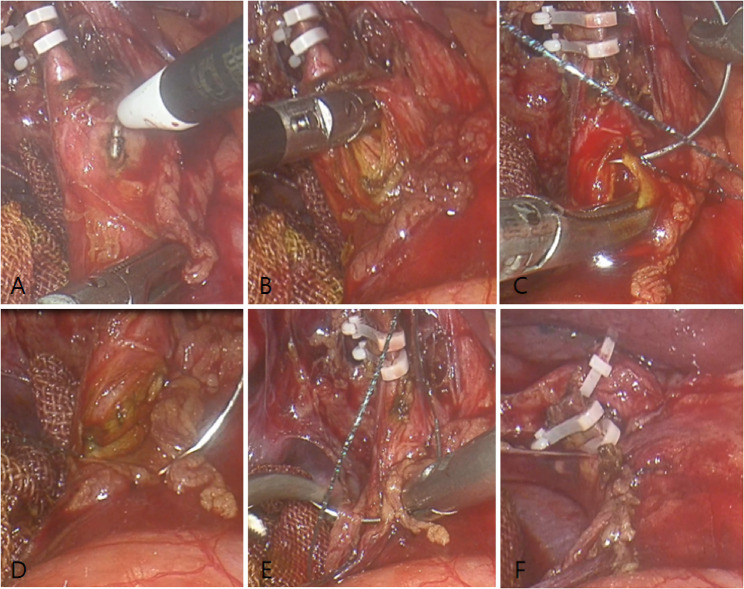

Background: Laparoscopic common bile duct exploration and primary suture (LBEPS) offers advantages such as minimal invasion, shorter operative time, and faster postoperative recovery in the treatment of common bile duct stones.However, its safety in elderly patients remains controversial.

Methods: A retrospective analysis was conducted on the clinical data of 128 patients with common bile duct stones who underwent LBEPS treatment in our hospital from December 2018 to March 2025.The patients were divided into an elderly group (≥ 65years, n = 55) and a non-elderly group (< 65years, n = 73) based on age.Baseline characteristics, operative time, postoperative complications, recurrence rate, and other indicators were compared between the two groups.